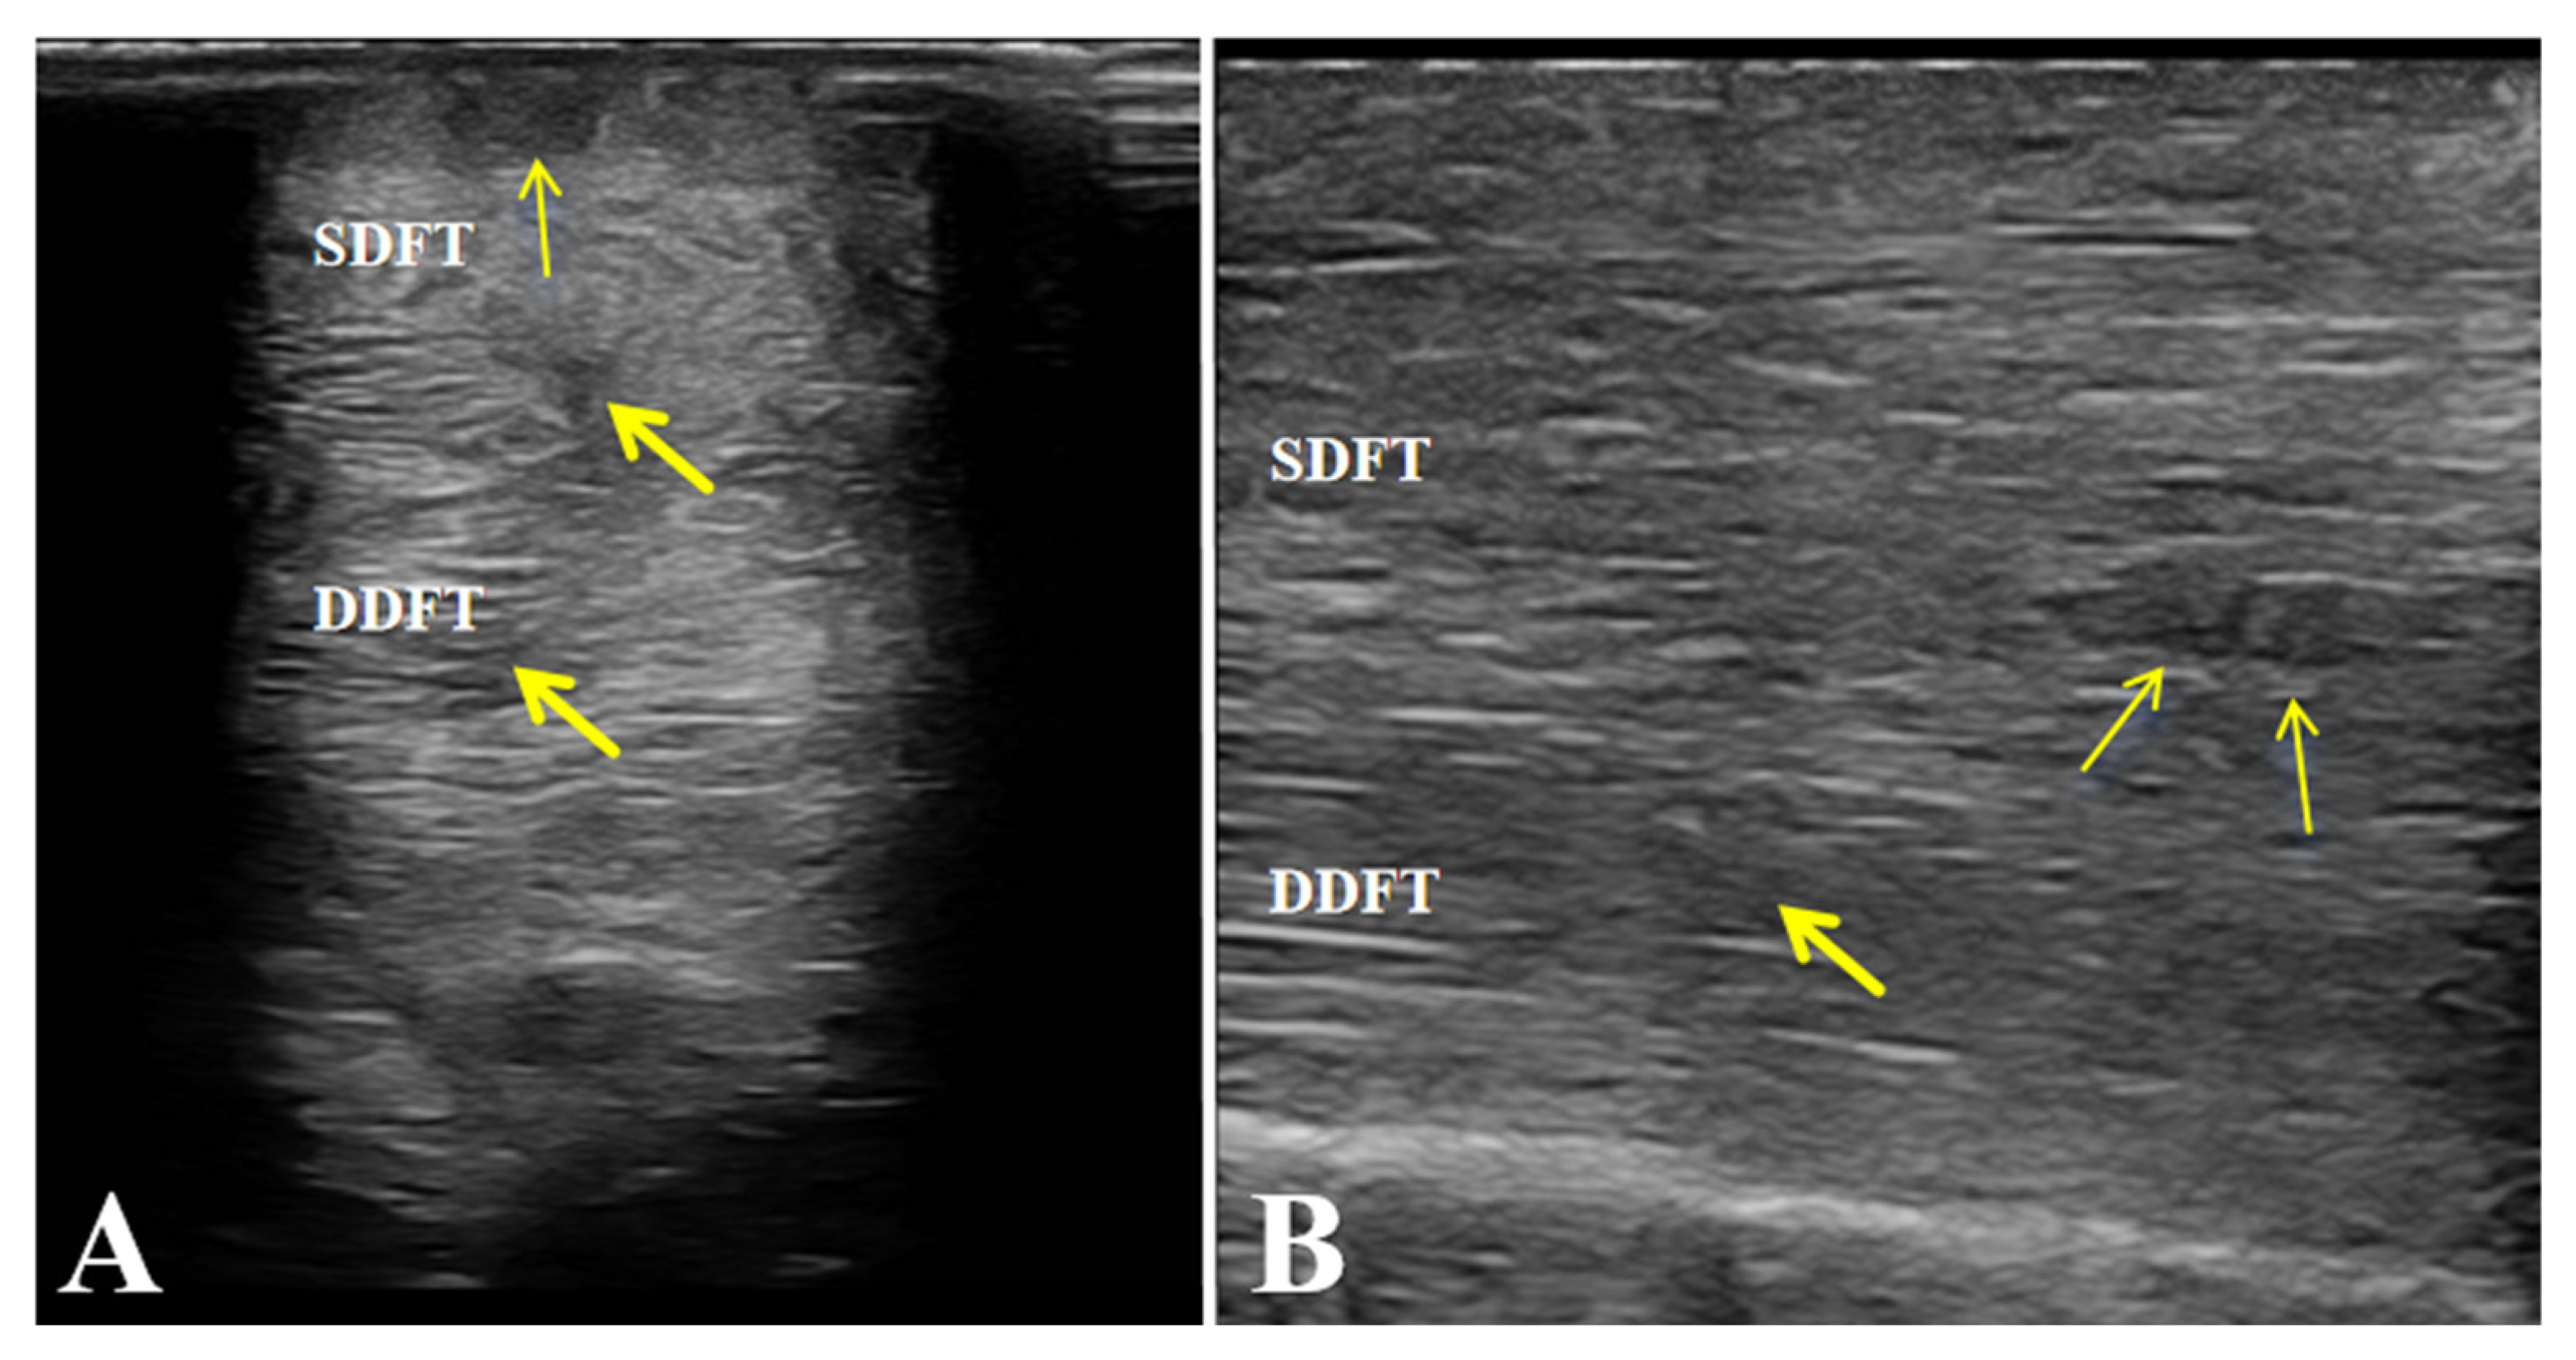

3.2.2. Ultrasound Examination

Ultrasonographic examination of the affected limb (left forelimb) showed a marked increase in the cross-sectional area of both the superficial digital flexor tendon (SDFT) and the deep digital flexor tendon (DDFT) compared with the contralateral side. The tendon margins were still visible, although slightly roughened. The normal parallel fibrillar echogenic pattern was almost completely lost and replaced by a diffuse, heterogeneous, mildly hypoechoic appearance. These findings indicate mild injury to both the SDFT and DDFT and are consistent with the diagnosis of flexor tendinitis (Figure 3).

Figure 3. Ultrasonographic features of the affected horse with flexor tendinitis. (a) Transverse sonograms of the superficial digital flexor tendon (SDFT) and deep digital flexor tendon (DDFT) (yellow arrow: lesion sites). (b) Longitudinal sonograms of the SDFT and DDFT (yellow arrow: lesion sites). Arrows indicate the sites of tendon injury.